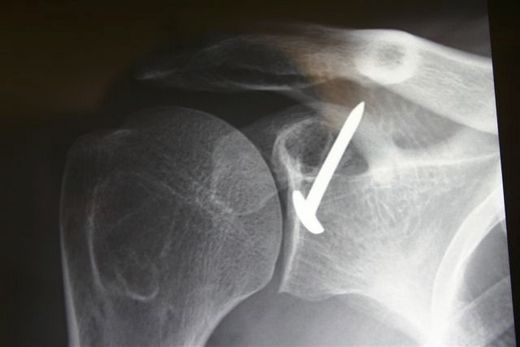

(unpublished data, courtesy of Gilles Walch) At the beginning of the 1950s, Albert Trillat, the head of the orthopedic surgical clinic at the Edouard Herriot Hospital in Lyon (France) and also the promoter of the "no touch technique", reported combination of an anterior labro-ligamentous complex reinsertion when feasible with a reduction of a so-called coraco-glenoid outlet by means of a coracoid osteoclasy and nail fixation (Figures).[14]

Postoperative anteroposterior X-ray of a right Trillat.